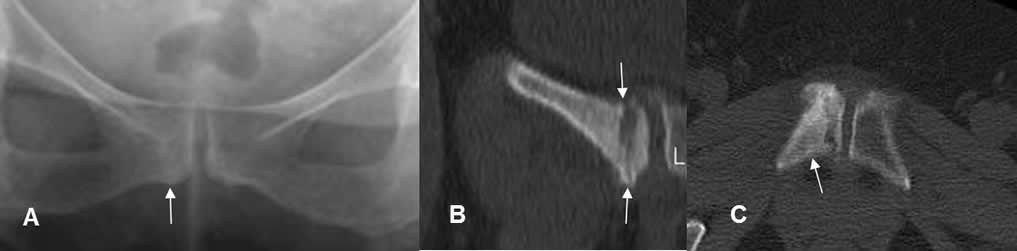

Fig 80 A. Reparación.

A: Rx AP. Zona de esclerosis en el pubis derecho.

B: TAC reconstrucción coronal. Fractura no desplazada del pubis, con formación de callo óseo inmaduro.

C: TAC axial. Esclerosis del hueso, por el proceso de reparación.